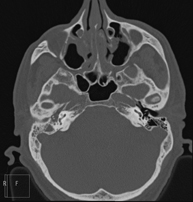

- Paranasal Sinuses CT

Radiological test that provides high definition anatomical images of the paranasal sinuses using CT (Computed Tomography) equipment. Indicated for: headache, mucus, facial infections.

- Temporal bone CT

Radiological test that provides high definition anatomical images of the temporal bone (inner, middle and outer ear) using CT (Computed Tomography) equipment. Indicated for: sudden or chronic hearing loss, vertigo, dizziness, congenital malformations.